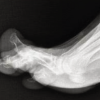

A 41-year-old male who was on irregular treatment for Gout presented to us with swelling around the base of the great toe and adjacent foot, which was progressively increasing in size leading to gross deformity and difficulty in walking (Fig. 1). The Patient does not give the history of alcohol intake. A radiograph of the right foot showed arthritis of the first MTP joint with subarticular erosions and sclerosis of adjacent bones consistent with gouty arthritis. On the left side, radiographs revealed an expansile lytic lesion involving the first metatarsal and entire proximal phalanx along with total destruction of the first MTP joint. Serum uric acid levels were elevated (10.3 mg/dL) consistent with gouty arthritis. Other blood parameters included elevated erythrocyte sedimentation rate (26 mm/h), elevated C-reactive protein (22 mg/L), Hb (13 g%), and total count (7600 cells/cumm). The previous treatment history was unclear, but the patient was taking allopurinol irregularly and native medicines. There were no neurovascular deficits. Although the history of gout and classical involvement of the right side pointed to the possibility of gout, there was a suggestion of alternate possibilities, such as chondrosarcoma, aggressive giant cell tumor, and tuberculosis for the left side lesion in view of the nature of destruction. Hence, magnetic resonance imaging (MRI) of the left foot was done, which was suggestive of tophaceous deposition (Fig. 2). An incision biopsy was done from the left side which confirmed gout. The patient also had tophaceous deposits in the ankle and both knee joints. Our next challenge was to excise the tophaceous deposits and reconstruct the massive defect. The patient underwent two-stage procedures (Fig. 3). The right side was operated first, as we contemplated a better prognosis on the right side while we were thinking of the possibility of amputation of the first ray on the left side. On the right side excision of the MTP joint along with the removal of all the tophi in surrounding tissues as well as an adjacent proximal phalanx and first metatarsal was done and the resultant bony defect was bridged with tricortical iliac crest autograft to maintain the length of 1st ray and achieve fusion of the first MTP joint. The limb was placed in a below-knee plaster slab for 3 weeks. Post-operative management included limb elevation and prophylactic antibiotics of 3 doses. Sutures were removed after 2 weeks, and there were no wound-related complications. The patient was mobilized non-weight bearing with a walker after wound healing and partial weight bearing after 5 weeks. Encouraged by good results on the right side, we decided to reconstruct the first ray on the left side, and a second surgery was done 2 months after the first surgery. The entire mass of lesion containing the first MTP joint, adjacent proximal phalanx, and near total first metatarsal along with soft tissue deposits were removed and extensor tendon of the great toe was sacrificed. The size of defect was measured and reconstructed with a fibular auto graft which was stabilized with K-wires between the stump of the first metatarsal and distal phalanx. The patient was treated with a below-knee plaster slab for the left side and non-weight bearing for 6 weeks followed by gradual weight bearing with a walker. There were no wound-healing problems on both sides. The patient was able to walk without support 3 months after the second surgery. The patient was also placed on medical treatment with Febuxostat 80 mg/day which was reduced to 40 m/day after 6 months. At 6 months follow-up, the patient had good relief of pain and was able to walk comfortably, while X-ray shows the incorporation of fibular graft and fusion across the distal phalanx and a stump of first metatarsal on the left side and incorporation of iliac crest graft on the right side (Fig. 4). The patient is allowed to resume work within his comfort, and adviced to continue febuxostat 40 mg once a day with regular monitoring of serum uric acid levels.